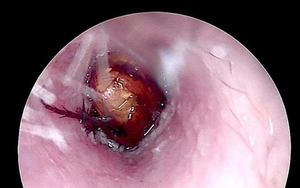

Hình ảnh chụp X-quang và dị vật được lấy ra khỏi hậu môn của bệnh nhân - Ảnh: BVCC

Theo các bác sĩ, dị vật được xác định là một chiếc chày dài khoảng 18cm, đường kính 6cm. Thách thức lớn nhất đối với ê-kíp là kích thước dị vật khá lớn, đồng thời bị hút chặt bên trong do hiện tượng giống “hiệu ứng chân không”, khiến việc lấy ra gặp nhiều khó khăn.

Sau khoảng 45 phút, dị vật đã được lấy ra an toàn. Khu vực tổn thương chỉ bị xây xát nhẹ và chức năng cơ thắt được bảo tồn.

Hình ảnh chiếc chày được lấy ra từ hậu môn của bệnh nhân.